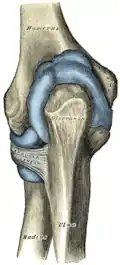

На дистальном эпифизе расположен мыщелок (лат. condylus humeri) и по бокам от него два надмыщелка — медиальный и латеральный (лат. epicondylus medialis et lateralis). Между надмыщелками располагается поверхность для сочленения с костями предплечья, разделённая на блок плечевой кости (лат. trochlea humeri) и головку мыщелка плечевой кости (лат. capitulum humeri). Выше них на передней стороне соответственно располагаются венечная (лат. fossa coronoidea) и лучевая (лат. fossa radialis) ямки, а также сзади локтевая ямка (ямка олекранона, лат. fossa olecrani), которые необходимы для сочленения с локтевой и лучевой костями, образуя локтевой сустав. На задней стороне медиального надмыщелка проходит борозда локтевого нерва (лат. sulcus nervi ulnaris)[4].

Соединение с костями предплечья. Вид спереди